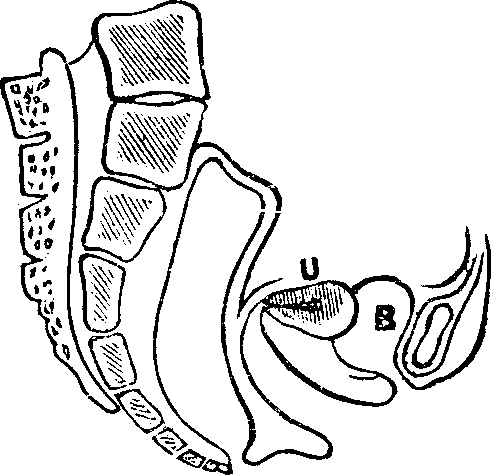

Fig. 10. Flexion, u, Uterus, B, Bladder.

Flexions and Versions of the Womb. Flexion of the uterus, in which it is bent upon itself, as illustrated in Fig. 10, produces a bending of the cervical canal, constricting or obliterating it, and thus preventing the passage of spermatozoa through it. Version of the uterus [pg 710]in which its top, or fundus, falls either forward against the bladder (anteversion), as illustrated in Fig. 11, or backward against the rectum (retroversion), may close the mouth of the uterus by firmly pressing it against the wall of the vaginal canal, and thus prevent the passage of spermatozoa into the womb. 'The treatment of these several displacements will be considered hereafter. We may here remark, however, that they can be remedied by proper treatment. Our mechanical movements, manipulations, and kneadings are invaluable aids in correcting these displacements.